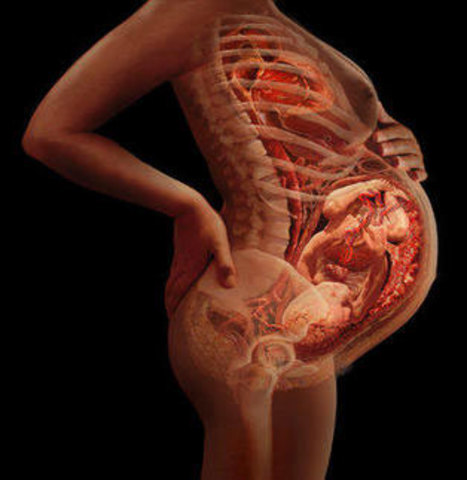

El feto se va a colocar para salir: con la cabeza hacia abajo.

El bebé ocupa ahora casi todo el sitio del útero y se entrena a abrir los ojos y a respirar. Sus movimientos, cada vez menos frecuentes.

Los huesos ya están desarrollados, pero aún son blandos y flexibles. Para dotarles de firmeza, el bebé comienza a almacenar hierro, calcio y fósforo.

En el sistema digestivo, el hígado, el estómago y el intestino van asumiendo progresivamente sus funciones.